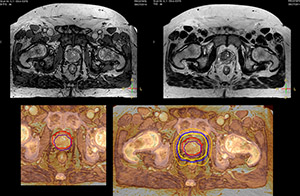

“We currently use MR-RT mainly in the abdomen and pelvis region: prostate, colorectal, pancreatic, cervical, and liver. Also in the brain, we are starting to use it,” says Dr. Yan.

MR imaging for brain treatment planning

“Also in brain tumor treatment planning the MRI soft tissue contrast offers a great advantage for seeing the target boundary. Brain tumors often involve edema, and CT cannot show this. Besides, MR also provides diffusion and perfusion information on background tissue,” says Dr. Yan.

“MR is a powerful method for imaging brain tumors. I think we should never treat a brain tumor without having good MR imaging we can trust,” Dr. Stevens says.